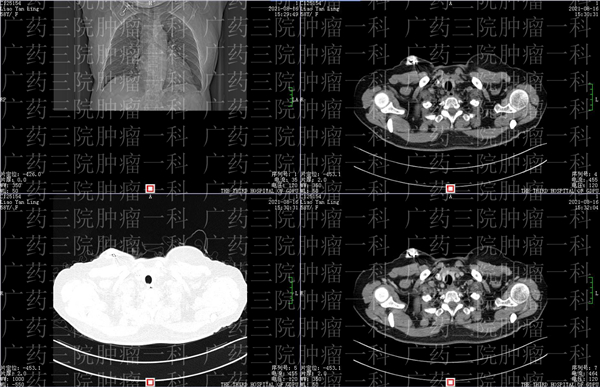

2019 年,廖女士无意间发现,自己的右乳上有一个小小的肿块,但这个肿块真的太小了,仅有 1cmX0. 5cm ,所以当时廖女士并不以为意。但在两年后,今年 2 月份,一次增强 MR 检查提示廖女士,她的双侧乳腺呈不均匀致密型,两年前发现的右乳肿物,可疑恶性,右侧的腋窝也有稍大的淋巴结,医生暂时考虑可能是转移。

于是,在医生的帮助下,廖女士进行了右乳乳腺肿块穿刺活检,病理的结果显示,廖女士右乳肿物的病理,结合免疫组化结果,符合浸润性导管癌。

不仅如此,廖女士右腋窝下淋巴肿块的穿刺物活检里,有大部分区域也符合浸润性癌,基本可以判断,廖女士确诊右乳恶性肿瘤并淋巴结转移。

两年的时间,一个小小的仅 0.5 厘米的小肿块,就变成了癌症,并且已经出现了转移。